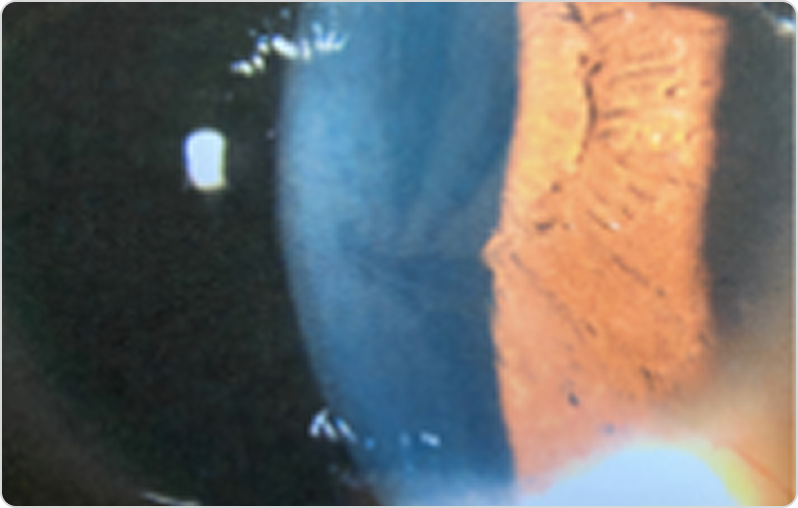

1. Қасаң қабық:

Құйынтәрізді кератопатия (cornea verticillata) — 75–98 % пациенттерде кездесетін ең жиі офтальмологиялық белгі: алтын-қоңыр түсті «вортекс» суретін түзетін құйынтәрізді субэпителиалдық шөгінділермен сипатталады. Бұл биомикроскопия (саңылаулы шам) әдісімен анықталатын маңызды диагностикалық белгі.44

Cornea verticillata (қасаң қабық эпителийіндегі құйынтәрізді паттерні бар бұлдыр шөгінділер) — Фабри ауруының тән белгісі.45

Фабри ауруы кезіндегі cornea verticillata бар қасаң қабықтың фотосуретіФабри ауруы кезіндегі cornea verticillata бар қасаң қабықтың фотосуреті

5-сурет. Оң көздің саңылаулы шамдағы фотосуреті: қасаң қабықтағы құйынтәрізді суреті бар диффузды қоңырқай шөгінділер (cornea verticillata); өзгерістер екіжақты.

Дереккөзден бейімделген: Salazar P. Clin Insights Eye Care. 2023;1(1). © 2023 Salazar P. CC BY 4.0.45